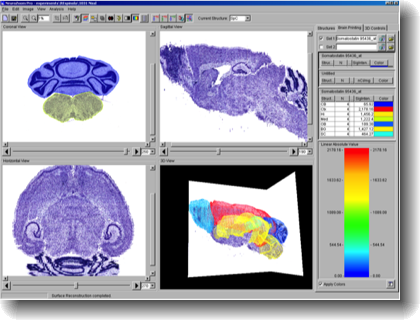

Once the sections are aligned and stored in the database, they may be refactored into other planes for orthogonal viewing and analysis.

The structured that are located in BrainArchive are easily navigated with software controls.

With properly segmented brain regions and structures, additional gene expression data can be visualized from BrainArchive.